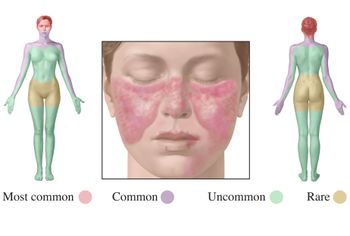

In patients with moderate to severe systemic lupus erythematosus (SLE), anifrolumab (AstraZeneca) was superior to placebo for improving overall disease activity, skin disease and oral corticosteroid tapering, say researchers writing in the New England Journal of Medicine.

Nearly one third of patients with systemic lupus erythematosus use prescription opioids, with around two thirds of those using opioids for more than a year, while emergency department use is associated with increased prescription opioid use, say researchers writing in Morbidity and Mortality Weekly Report in Septmeber.